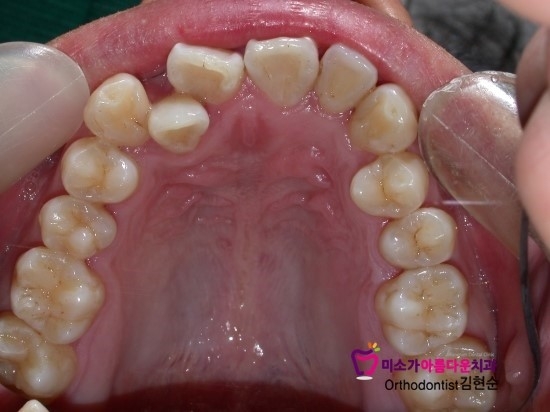

한국인들은 구강 구조에서 많은 비율을 차지하는 것이 바로 돌출입인데

덧니, 돌출 교정의 경우 충분한 공간을 필요로 하기 때문에

2~4개 가량의 치아를 발치하는 교정방식을 선택하는 경우가 많습니다.

발치로 7~8m 정도의 빈공간이 생기면

이 공간으로 앞니를 이동시키고 고르게 편 뒤에 빈 공간을 닫고

돌출되었던 앞니를 후방으로 이동시키는 것입니다.